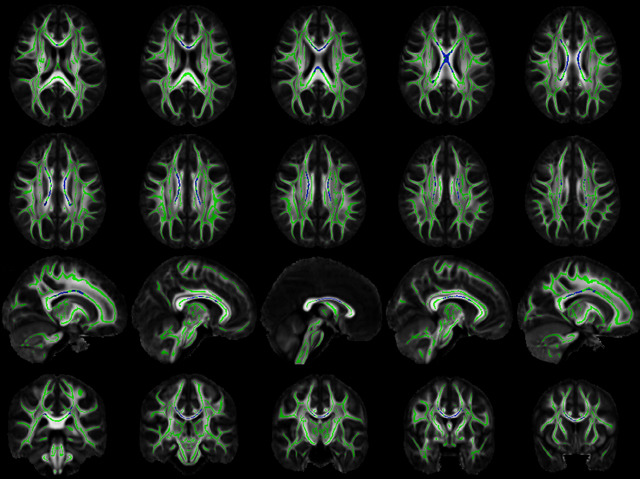

“Use your grey matter,” an annoying person might say, pointing to the mass of communicating brain cells (neurons) inside your skull. Yet the lesser-known white matter in our brains is equally important to thinking clearly. Outlined in green in these dMRI brain scans, white matter is made up of bundles, or tracts, of neuron bodies. Bunched together like electrical cables, they carry messages between areas of grey matter – where the neuron ends communicate. An area of white matter, highlighted here in blue, is often found damaged inside elderly brains. Pictured from different angles and depths here, the damage affects part of the brain called the corpus callosum, where neurons controlling spatial awareness are bundled. Age brings inflammation to the corpus callosum – often eroding the neurons’ natural insulation, myelin – which may explain how spatial perception requires more careful thought as we grow older.